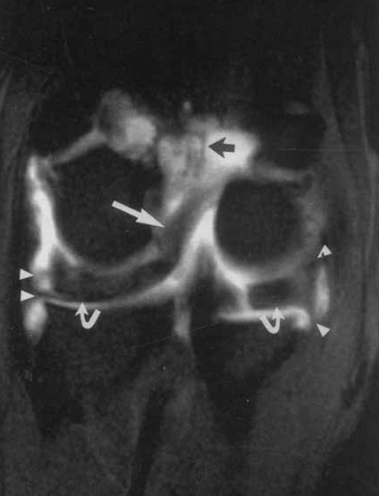

What do the curved lines represent and the arrow heads?

Meniscus - curved line

Meniscal struts - arrow heads